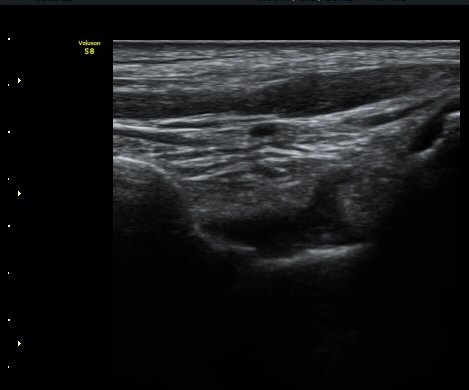

Á¾µ¹ºñ°ñÀδë Á¾´Ü¸é°Ë»ç¿¡¼­ Á¾°ñºñ°ñÀδë´Â Á¤»óÀûÀÎ ¸ð¾çÀ¸·Î °üÂûµÈ´Ù(±×¸² 3, 4).